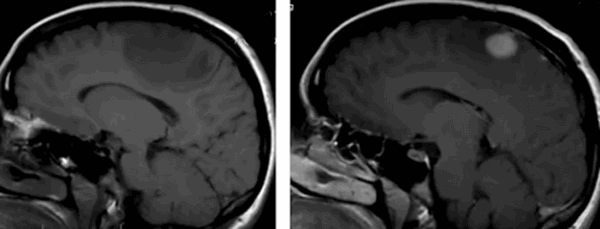

Глиобластома на МРТ головного мозга без контраста

До- и постконтрастное изображение злокачественной опухоли головного мозга